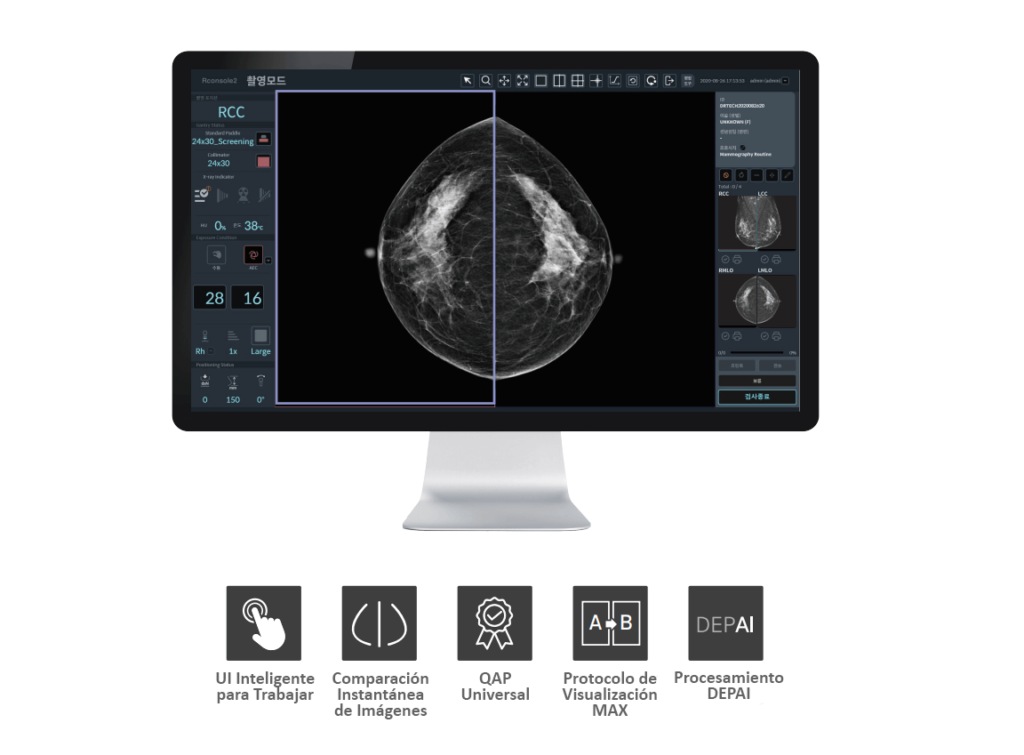

Rconsole2: AIDIA

Herramientas avanzadas de visualización y parámetros de imagen

- Herramienta de ajuste de parámetros de imagen: Herramienta sencilla de configuración de parámetros de imagen para personalizar la configuración del estilo de imagen (se proporcionan 3 parámetros optimizados predeterminados).

- Comparación instantánea de imágenes: Compare los estilos de los parámetros de imagen antes y después al instante.

- Alineación automática del pezón: Visualización sencilla de la simetría de la imagen.

Cómoda gestión de pacientes e imágenes

- Protocolo de Colgado MAX: Comparación de varios protocolos de image.

- Máquina del Tiempo: Seguimiento fácil del paciente con recuperación de imágenes anteriores.

Protocolo de control de calidad global especializado en mamografía

- QAP universal: Admite más de diez protocolos QAP para el mantenimiento de la más alta calidad del sistema y de la imagen.

- Manual digital: Proporciona un manual digital para procedimientos de control de calidad fáciles y rápidos.

- Historial de QAP: Seguimiento del historial de informes QAP para el mantenimiento sistemático.